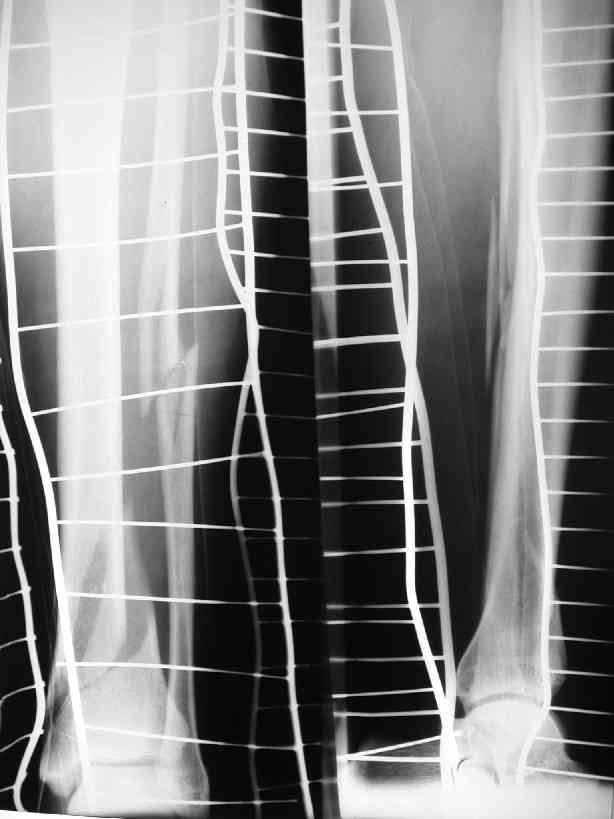

дистальный метафизарный перелом б/берцовой кости 43А1.1

Какой вид остеосинтеза выбрать? Пластину или гвоздь?